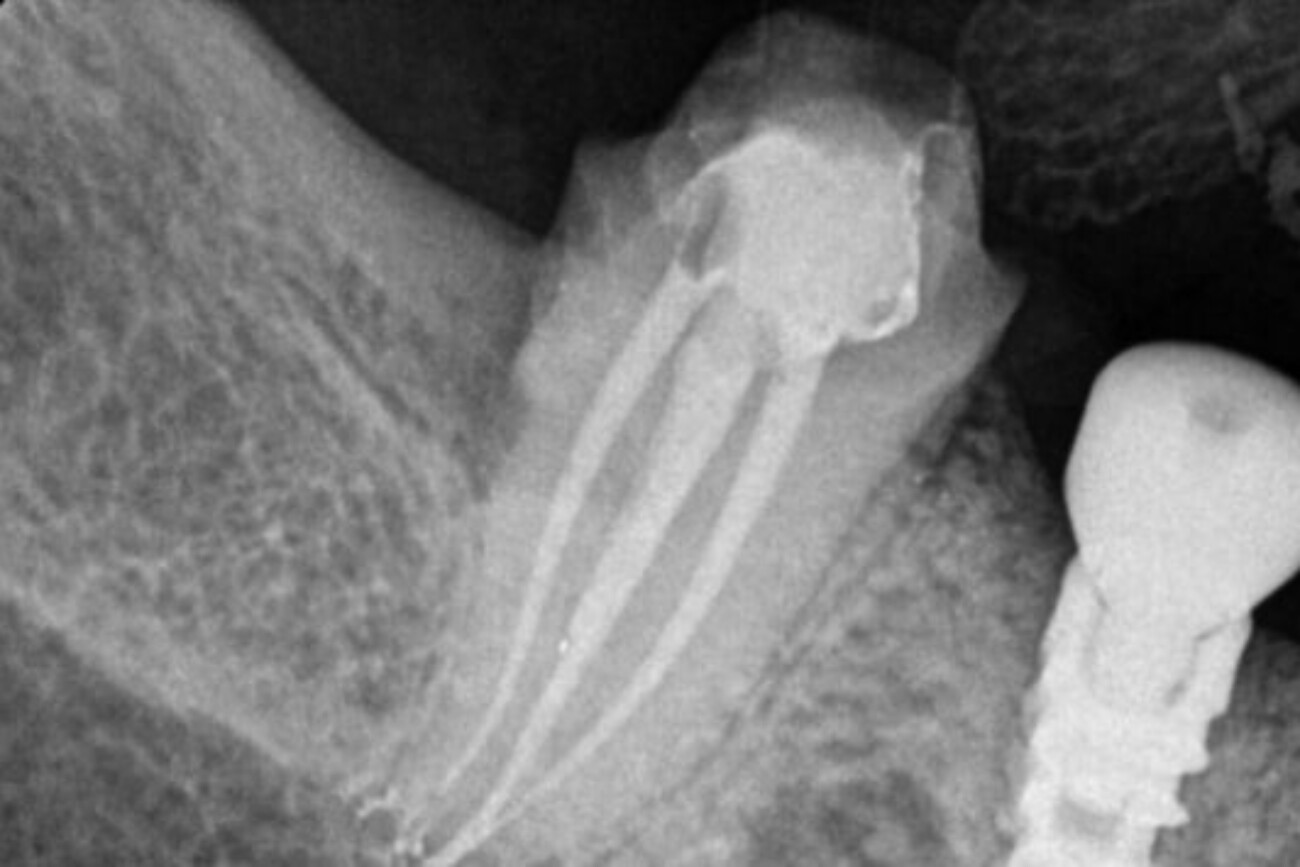

State-Of-The-Art Technology For

Root Canal In Tijuana

By incorporating advanced technologies, XDentistry ensures that root canal treatments are not only efficient but also highly precise, tailored to each patient’s unique dental needs. This commitment to cutting-edge advancements guarantees optimal outcomes and patient satisfaction.

CAD/CAM (Computer-Aided Design/Computer-Aided Manufacturing):

Allowing for the precise design and creation of dental restorations, including crowns post-root canal. This technology ensures a custom fit and optimal functionality for restored teeth.

3D CBCT for Teeth Scanning:

Providing detailed 3D images of the teeth and surrounding structures. This aids in diagnosing complex root canal cases by offering a comprehensive view, enabling precise treatment planning.